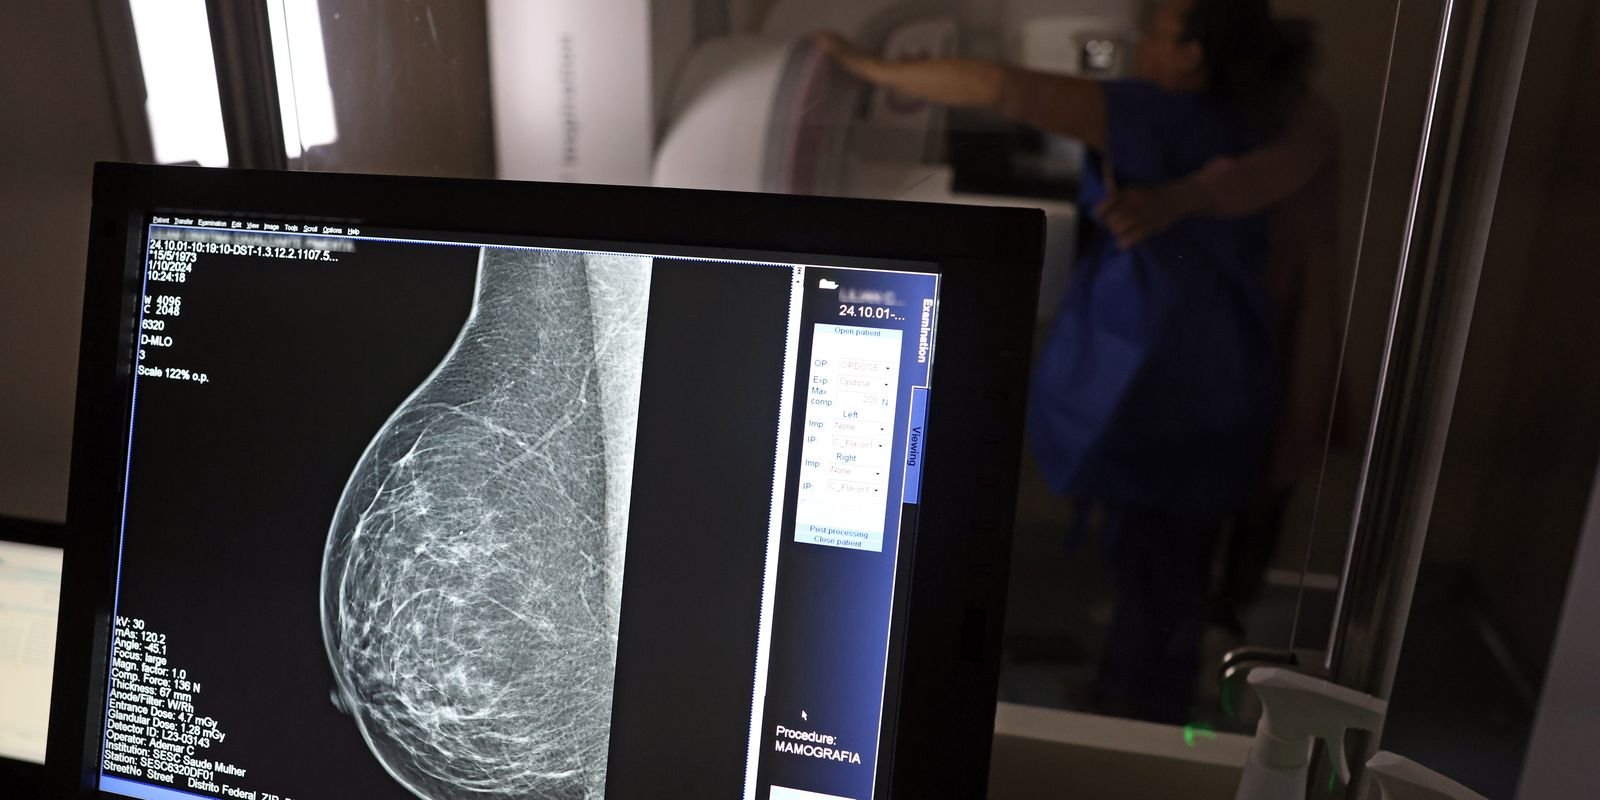

O Ministério da Saúde passou a recomendar o acesso a mamografia, via Sistema Único de Saúde (SUS), para mulheres de 40 a 49 anos – mesmo que não haja sinais ou sintomas de câncer de mama. De acordo com a pasta, a faixa etária concentra 23% dos casos da doença, e a detecção precoce aumenta as chances de cura.

Até então, a orientação era que o exame fosse feito a partir dos 50 anos.

As mamografias via SUS em pacientes com menos de 50 anos, de acordo com a pasta, representam 30% do total, o equivalente a mais de 1 milhão apenas no ano de 2024.

Os números mostram que, em 2024, cerca de 4 milhões de mamografias para rastreamento e 376,7 mil exames diagnósticos foram realizados no SUS.